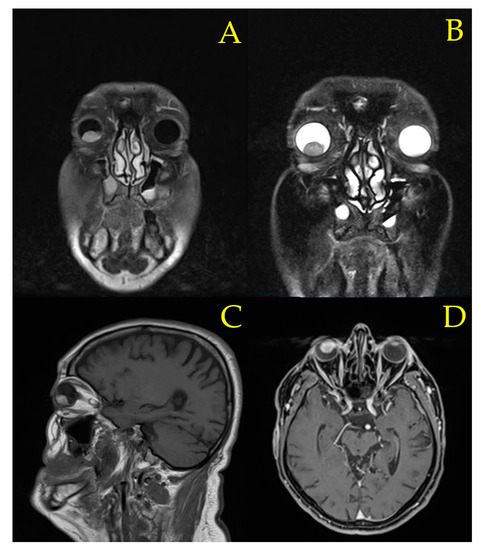

Case Presentation